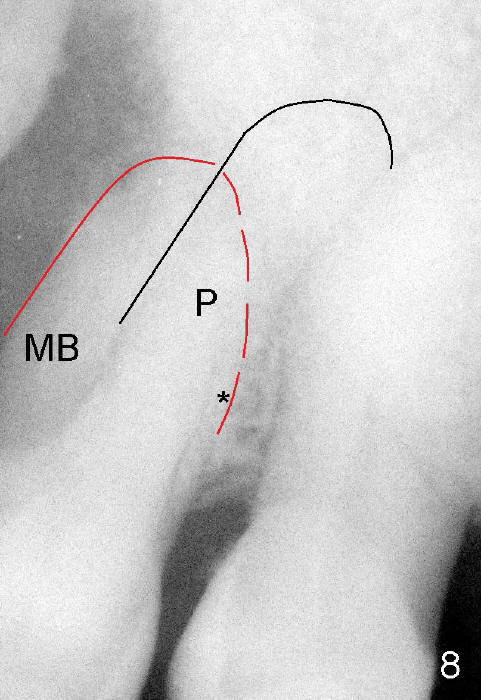

这种前臼齿牙根分布有点象上颌磨牙。颊侧两个根近远中宽度比鄂侧根宽(图四至图六),这个现象同样表现在X光片上(回到图一,图二),图七,图八是图一,图二放大,显示颊侧根(MB和*)比鄂侧根(P)宽,图八红线代表颊侧根根尖,黑线鄂侧根根尖。